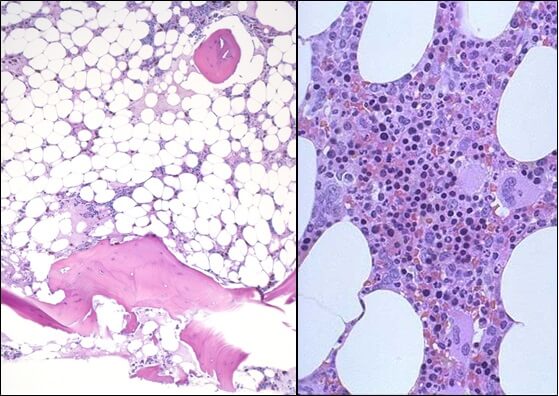

Это заболевание впервые было описано в 1888 г. Паулем Эрлихом. Название апластическая анемия был предложено в 1904 г. Чауфордом. Частота ежегодной встречаемости заболевания от 6 до 13 случаев на 1 000 000 населения. Апластическая анемия (АА) – заболевание крови, при котором в результате угнетения костномозгового кроветворения формируется панцитопения [1]. Иммунная агрессия, направленная на гемопоэтические клетки – предшественники за счет активности Т-лимфоцитов и киллеров, является основным механизмом нарушения кроветворения при апластической анемии. Отмечается гиперпродукция цитокинов, подавляющих гемопоэтические клетки и стимулирующих активацию Т-лимфоцитов [2]. В микропрепаратах костного мозга при апластической анемии отмечается полное опустошение костного мозга, присутствуют мелкие очаги гемопоэза [3]. Микроокружение костного мозга играет большую роль в развитии гемопоэтических клеток и в функционировании костного мозга, которое в свою очередь зависит от сети микроциркуляции мозга. Плотность сосудов костного мозга (плотность микроциркуляции) у больных с апластической анемией низкая. Это играет определенную роль в патофизиологии недостаточности мозга. Не исключено, что применение проангиогенных агентов в терапии апластической анемии сыграет определенную роль в восстановлении функции костного мозга.

- Исследованиепунктата костного мозга. В миелограмме обнаруживается уменьшение количества миелокариоцитов и мегакариоцитов, снижение клеточности. В трепанобиоптате определяется замещение красного костного мозга жировым (желтым).